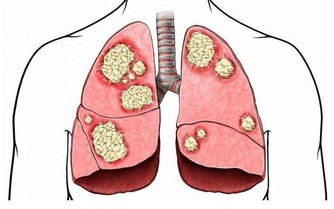

夏季由於排汗、無食慾等原因,會引起癌症患者身體免疫功能下降,

因而影響免疫細胞抵抗細胞侵害的能力,容易出現癌細胞激素擴散、轉移,病情加重的情況。